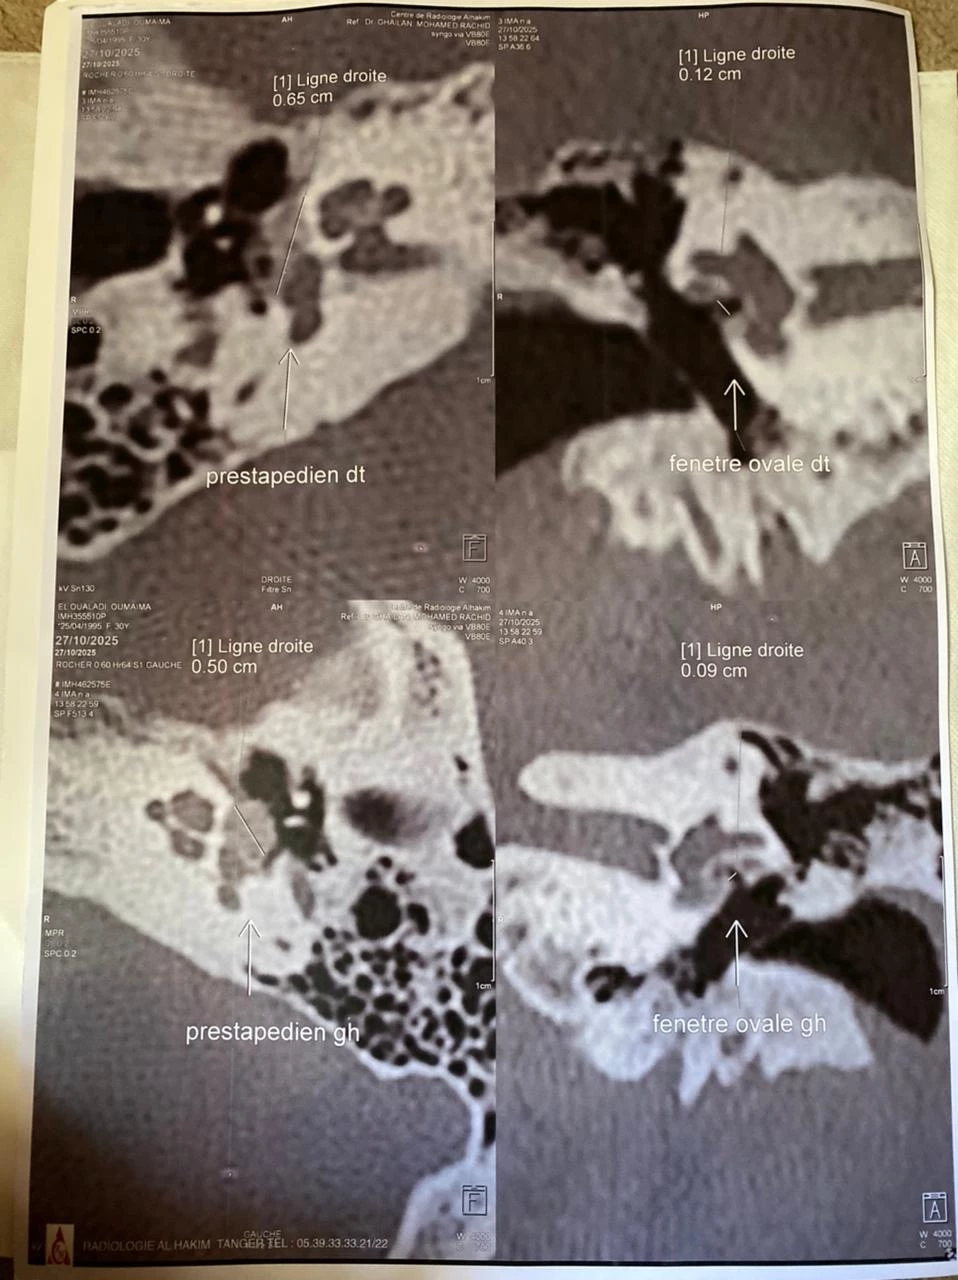

Oumaima El Oualadi, una joven hermana de Larache, Marruecos, enfrenta una difícil prueba. Padece otospongiosis, una enfermedad que provoca la pérdida progresiva de la audición.

Su oído izquierdo está gravemente dañado y los médicos le han indicado que debe operarse con urgencia para no perder completamente la audición. La intervención cuesta 1.500 € por oído. Aunque necesita tratar ambos, lo prioritario es salvar el oído izquierdo.